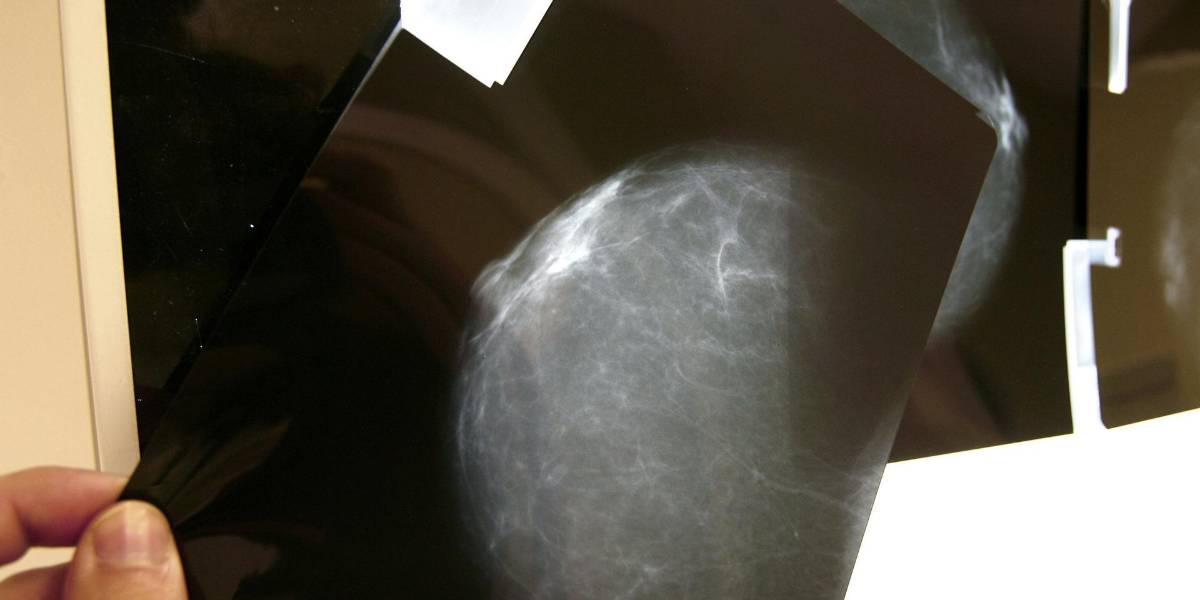

El cáncer de mama causará más de un millón de muertes en el 2050

El cáncer de mama se ha convertido en una de las principales causas de muerte entre mujeres en todo el mundo. Según la Agencia Internacional de Investigación sobre el Cáncer (IARC), una de cada 20 mujeres padecerá esta enfermedad a lo largo de su vida y una de cada 70 morirá por su causa.

En 2022 se registraron 2,3 millones de nuevos diagnósticos y 670 000 fallecimientos, pero las proyecciones indican que, para 2050, los casos aumentarán un 38 %, superando los 3,2 millones anuales, y las muertes podrían superar el millón, un incremento del 68 %.